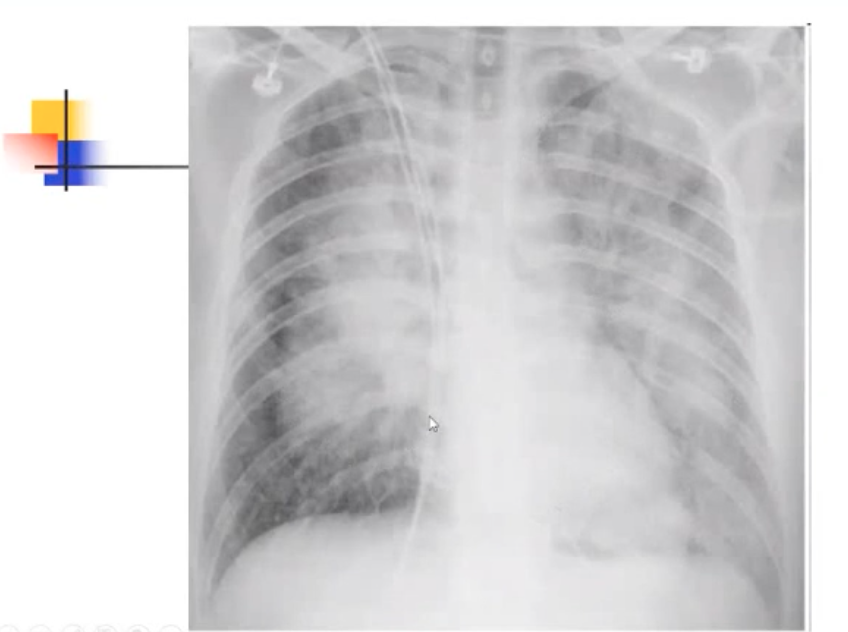

Hình ảnh XQ:

Giai đoạn phù phổi: hình ảnh hình cánh